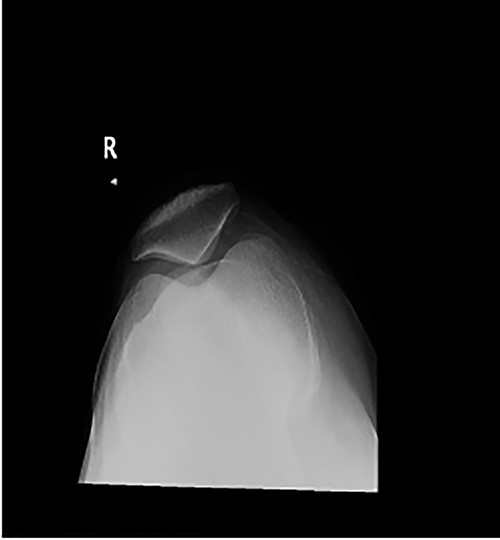

Long weight-bearing knee radiographs showed severe osteoarthritic changes, 18° knee genuvarum and extension deformity of the left distal femur (Fig. 2). Skyline view showed severe arthritic changes (Fig. 3).

Preoperative plain radiographs; (A) severe osteoarthritic changes affecting the left knee with narrowing of the medial knee joint compartment; (B) left femur with dorsal angulation above the condyles and severe patella baja.